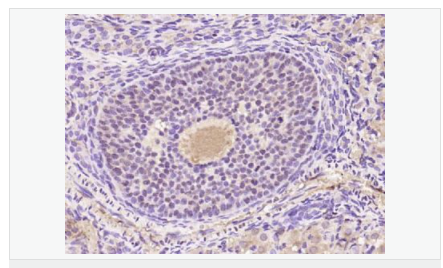

| 产品应用 | WB=1:500-2000 ELISA=1:5000-10000 IHC-P=1:100-500 IHC-F=1:100-500 Flow-Cyt=1μg /test IF=1:100-500 (石蜡切片需做抗原修复) not yet tested in other applications. optimal dilutions/concentrations should be determined by the end user. |